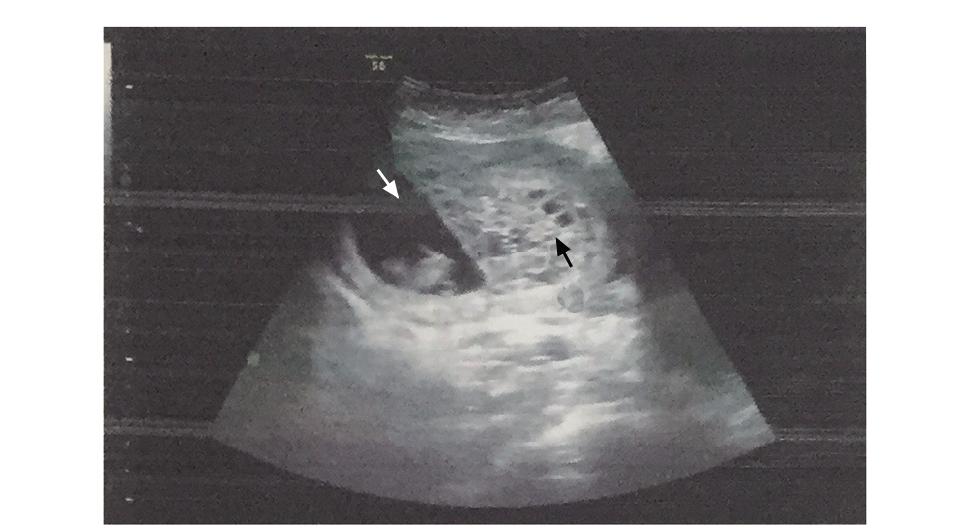

超声可见宫内妊娠囊(白色箭头)及葡萄胎组织(黑色箭头)